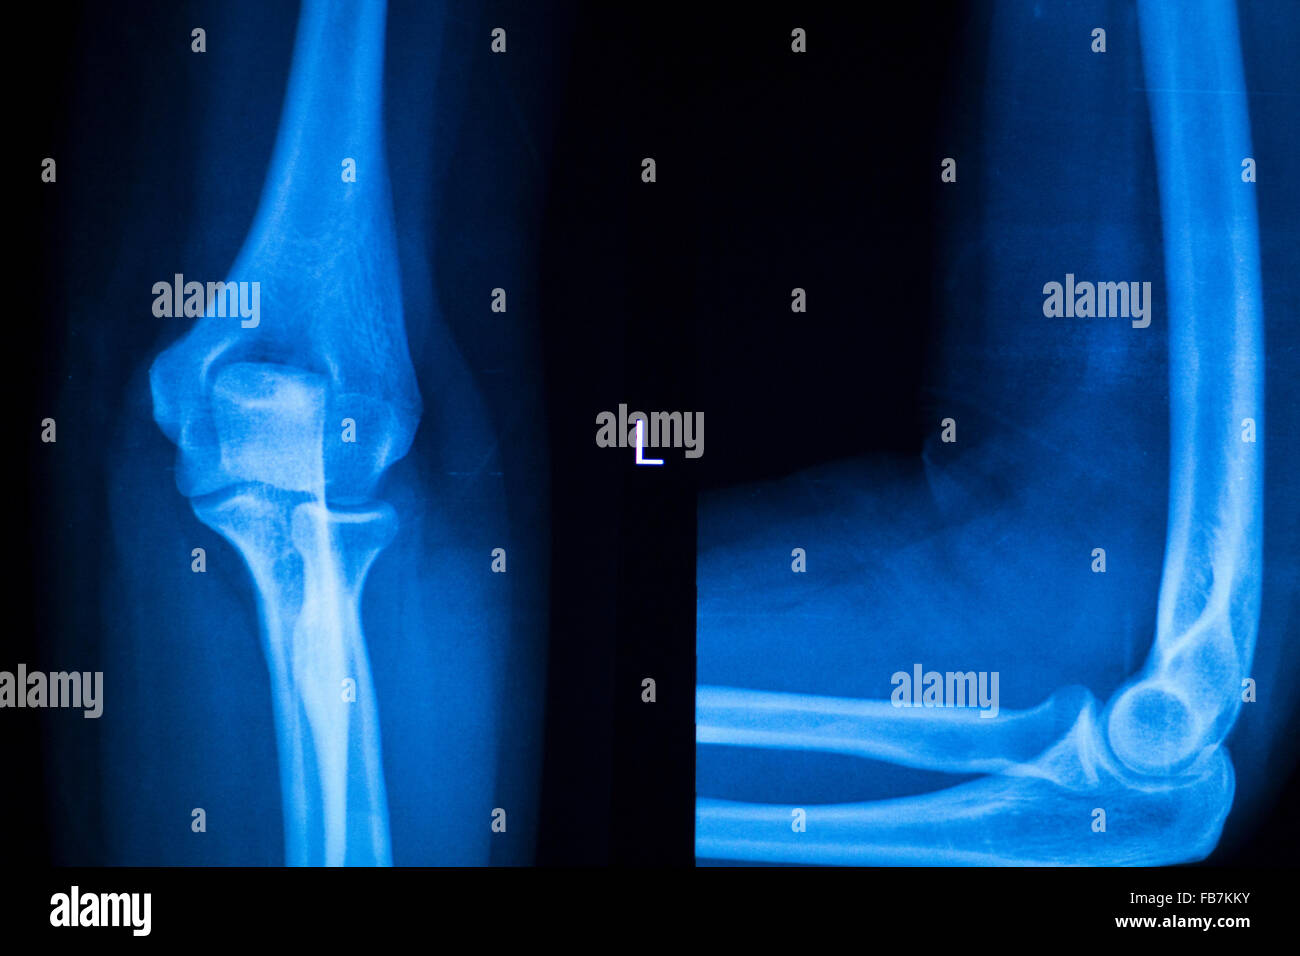

Fracture Elbow, forearm xrays image showing plate and screw fixation Elbow Surgery Plate And Screws The system features the hexalobe screw system with. The pieces are then put together and held. The patient does not follow. the fracture may pull apart and the screws, plates, or wires may shift or break. The acumed olecranon plates provide fixation for both fractures and osteotomies in the proximal ulna. Designed to provide an anatomic fit,. this. Elbow Surgery Plate And Screws.

From www.alamy.com